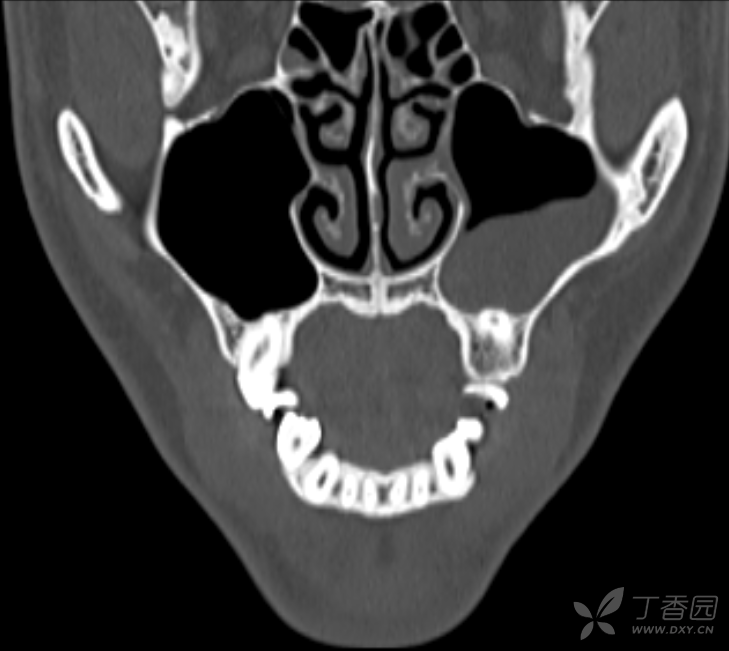

"牙源性"上颌窦囊肿一例,比较少见,求征集手术方案